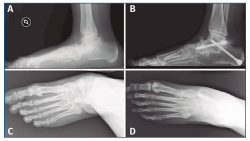

No se pudo realizar una valoración completa del resultado de la corrección clínica por no disponer de fotografías pre- y postoperatorias de todos los pacientes (Figura 5), aunque, como hemos comentado anteriormente, se valoró la evolución radiológica en la totalidad de los pacientes (Figura 6).

Figura 5. Aspecto clínico pre- (A y C) y postoperatorio (B y D) mostrando la corrección del valgo del pie izquierdo, así como la convexidad de la cara medial y el hundimiento del arco interno.

Figura 6. Aspecto radiográfico pre- (A y C) y postoperatorio (B y D) mostrando la corrección de las mediciones angulares.